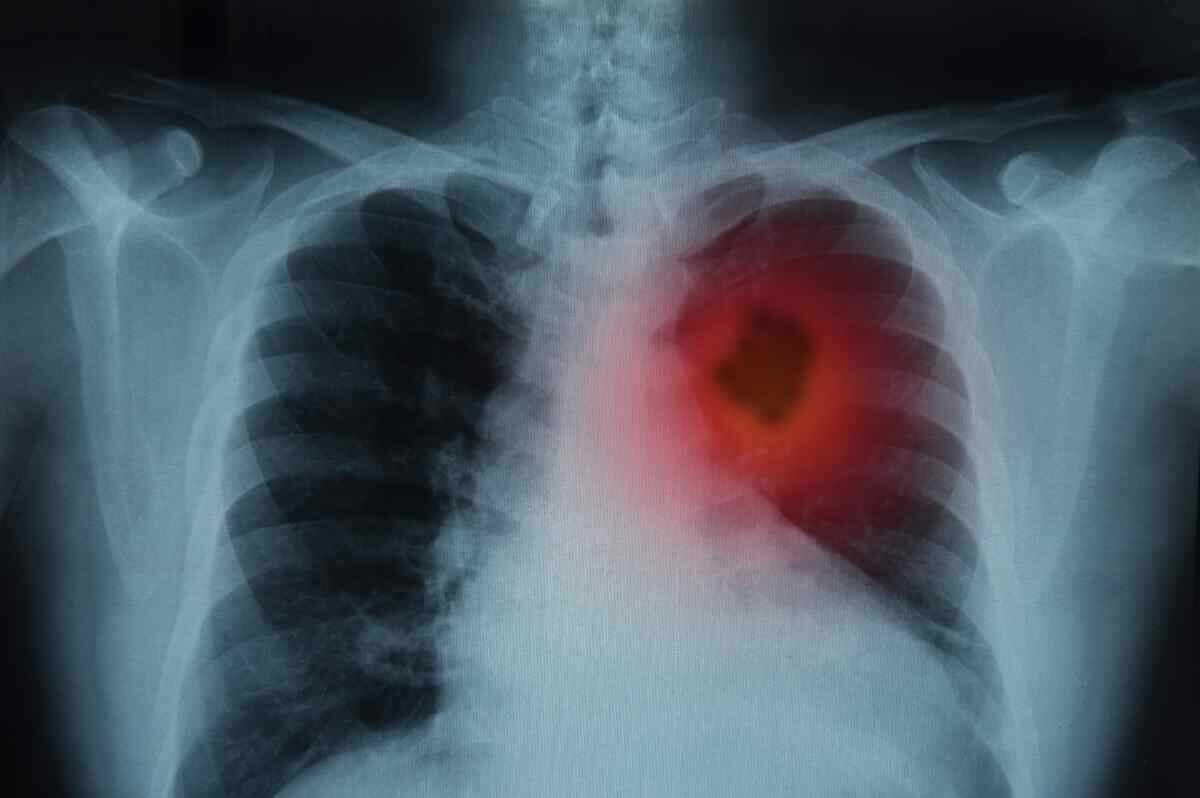

Kimsenin Umursamadığı Bu Belirti Kanserin İşaretiymiş

TÜMÖR GELİŞTİRME OLASILIĞI 6 KAT FAZLA Bilim adamları, kaşıntı şikayeti olan hastaların, tümör gelişme olasılığının altı kat daha fazla olduğunu keşfettiler. Özellikle karaciğer, safra kesesi, safra yolları, hematopoietik sistem ve deri tümörlerinin yaygın olduğu gözlemlendi. Ancak kaşıntısı olan hastaların hepsinde döküntü görülmedi. Araştırmacılar, özellikle lösemi, kemik tümörü, bronşiyal karsinom ve multipl miyelom hastalarında döküntüleri tespit edebildiler. CİLT DÖKÜNTÜLERİ VE TÜMÖR ARASINDAKİ BAĞLANTI ARAŞTIRILIYOR Bu tür tümörlerdeki mekanizmanın iltihaplı bir cilt reaksiyonuna dayandığı için, döküntüler ile tümör arasındaki bağlantıyı araştırıyorlar. Ancak bu çalışma, kaşıntının mı yoksa kanserin mi ilk önce ortaya çıktığını kesin olarak belirleyemedi. Daha ileri araştırmalara ihtiyaç duyulsa da, bilim insanları bu bulguların, doktorların belirsiz kaşıntı semptomlarını daha iyi anlamalarına yardımcı olabileceği konusunda iyimserler. Haberin devamını okumak için Lütfen sonraki sayfaya geçiniz...